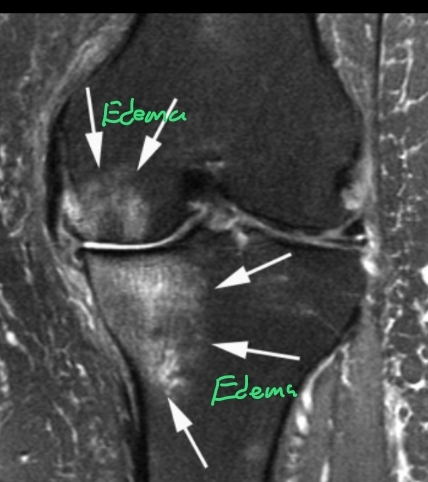

Mejor estudio para ver el pinzamiento femoroacetabular y qué se ve

A

RM

- Permite ver edema oseo

- Pinzamiento leve

- Quistes

- lesión del labrum